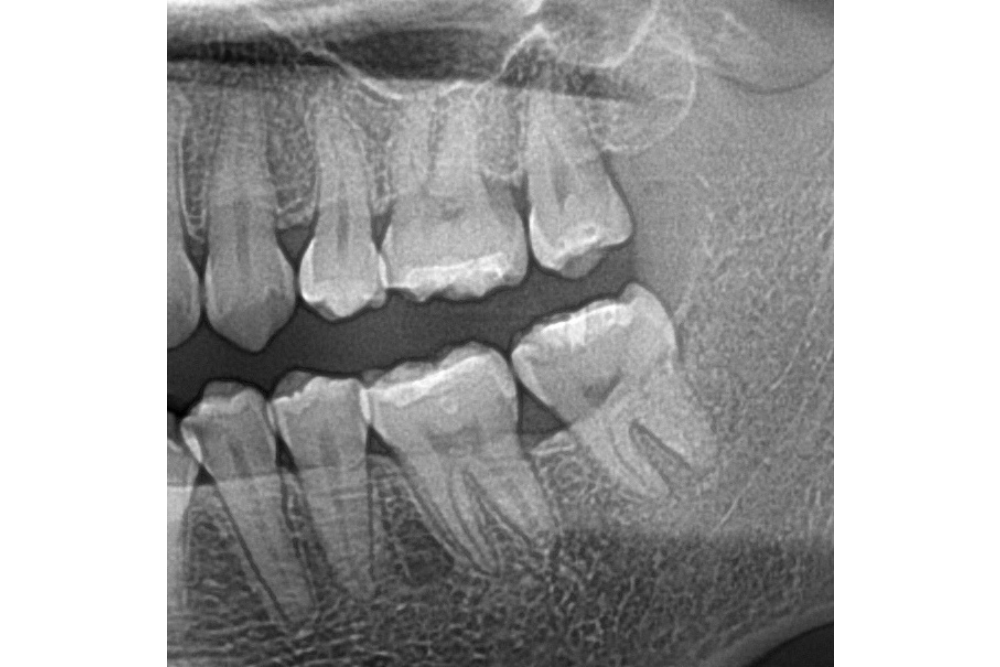

아래쪽 두 번째 어금니(제2대구치)가 선천적으로 없는 결손치로서, 사랑니(제3대구치)가 있으나 앞으로 쓰러져서 잘 안 씹히고 썩어 있습니다.

이런 경우 사랑니를 발치하고 임플란트를 하는 방법도 있으나, 본인 치아를 살리고 싶어하셔서 교정으로 접근하였습니다.

부분교정을 통해 누워있던 사랑니를 세웠으나, 씹는 면에 충치가 있습니다.

교정종료 후 보철치료(인레이)를 통해 씹는 기능을 회복시켰습니다.